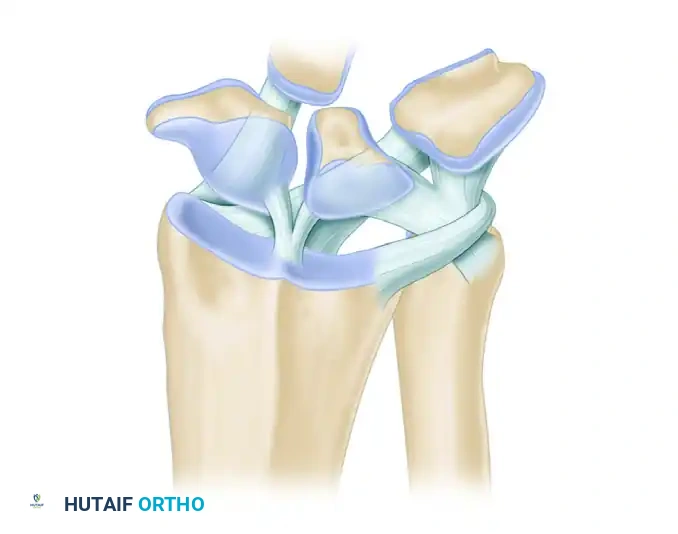

Osseous Architecture and Biomechanics

The distal radius articulates with the scaphoid and lunate via two distinct elliptical concavities: the scaphoid fossa and the lunate fossa, separated by the interfossal ridge. Crucially, the articular surface of the distal radius is not orthogonal to its longitudinal axis. It possesses a palmar tilt (volar inclination) of 11 to 12 degrees and a radial inclination of 22 to 24 degrees.

Ligamentous Anatomy

The palmar extrinsic ligaments are critical stabilizers of the radiocarpal joint and are clearly visible during the arthroscopic sweep. They appear as thick, capsular thickenings.

* Radioscaphocapitate (RSC) Ligament: The most radial palmar ligament, acting as a fulcrum for the scaphoid.

* Long Radiolunate (LRL) Ligament: Adjacent to the RSC, providing vital support to the lunate.

* Radioscapholunate (RSL) Ligament (Ligament of Testut): A neurovascular conduit rather than a true mechanical ligament, located between the LRL and the Short Radiolunate (SRL) ligament.

- Radial Sweep: Direct the arthroscope toward the distal end of the radius. Follow the articular surface along the scaphoid and lunate fossae, noting the integrity of the interfossal ridge.

- Scaphoid and Scapholunate Interval: Move the arthroscope in the radial direction to identify the proximal margin of the scaphoid. Carefully evaluate the scapholunate (SL) articulation. The normal SL joint appears as a small, tight crease between the scaphoid and lunate, with intimate blending of the interosseous ligament with the adjacent articular cartilage.

- Identifying Extrinsic Ligaments: Direct the 30-degree optic palmarly. Identify the stout palmar carpal ligaments. Moving from radial to ulnar, you will visualize the Radioscaphocapitate (RSC) ligament, the Long Radiolunate (LRL) ligament, and the vascular tuft of the Radioscapholunate (RSL) ligament. Use the probe to stress these ligaments and evaluate their structural integrity.